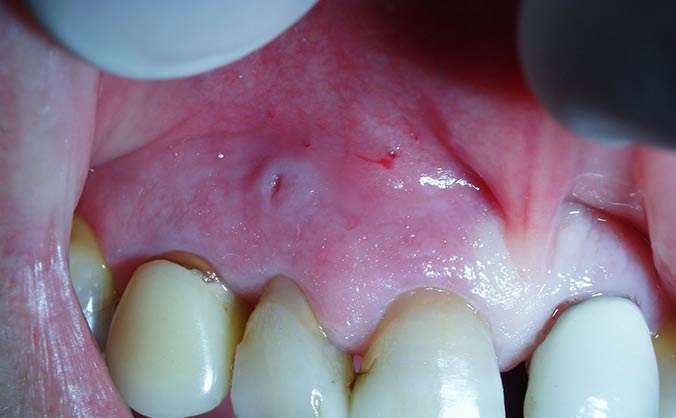

Хирургическое

Проводится при значительном разрастании опухоли посредством полного ее удаления. Операция подразумевает ее рассечение, и проходит в несколько этапов:

- Введение анестезии (в зависимости от клиники эпулиса, делается местное или общее обезболивание).

- Как только подействует анестетик, врач, отступив от ножки нароста 1-2 мм, надрезает вокруг него мягкие ткани десны на всю их глубину, захватывая надкостницу.

- Лоскут по всей окружности отслаивают.

- Если заболевание затронуло костную ткань, проводится препарирование пораженной области до здоровых тканей.

- Раневая поверхность прочищается, промывается антисептическим раствором и покрывается тампоном, пропитанным йодоформным составом.

- Если область поражения обширная, ее края стягиваются швами.

Расположенные рядом зубы вырываются только при их подвижности (при III степени) или при оголении их корней на 2/3 длины.